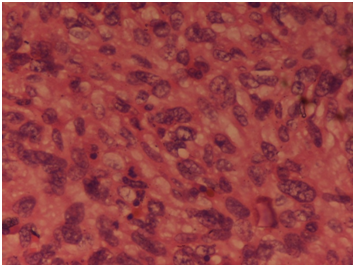

A 22-year-old married female presented in the gynecologic outpatient department with the chief complaints of difficulty in breathing and pain in the lower abdomen since a fortnight. She also complained of fever on and off since 20days with associated weight loss, weakness and fatigue. On physical examination, a mass was felt in the suprapubic region, about 20cm×15cm in size, firm and immobile on palpation. Her laboratory investigations revealed mild microcytic hypochromic anemia and leukocytosis (13,500cells/μl). Liver and kidney functions were normal. Urine analysis revealed no pathology. Pelvic ultrasound and computed tomography revealed a huge and heterogeneous pelvic mass containing solid and cystic areas with ascites measuring 16x13x9cm. Whole body scan revealed no other abnormality. Ascitic tap smear showed only degenerate cells with no viable malignant cells. Chest x-ray revealed left pleural effusion, which on aspiration cytology showed presence of atypical cells suggesting metastatic adenocarcinoma. The serum CA-125 level was markedly raised (126U/ml). Three cycles of neoadjuvant chemotherapy comprising of paclitaxel and carboplatin was administered to relieve her symptoms of breathing, followed by total abdominal hysterectomy with unilateral salpingo-oophorectomy. Laparotomy revealed an unilateral ovarian mass, grossly measuring 13cm×13cm×7cm in size with glistening white and slightly nodular outer surface. Cut surface showed homogenous grayish white solid and cystic areas along with hemorrhage and necrosis (Figure 1). Microscopically section from the tumor showed malignant fascicles of spindle cells with hyperchromatic and pleomorphic nuclei, 30mitosis/10 HPF mixed with areas of necrosis (Figure 2). Necrotic areas might be the carcinomatous component which was responsive to chemotherapy whereas the mesenchymal sarcomatous component was resistant to therapy. Foci of hemorrhage and cystic degeneration were also seen. Histologically, the major part of the tumor consisted of the sarcomatous component which was Van Geison (VG) positive (Figure 3) and showed weak diffuse vimentin positivity on immuno histochemistry (Figure 4). On the basis of clinical findings, gross and microscopic findings, a diagnosis of carcinosarcoma ovary was made.

Figure 4 Immunohistochemical staining showed weak diffuse positivity for vimentin. IHC Vimentinx40X.

It is challenging to differentiate primary ovarian carcinosarcoma pre- operatively from ovarian surface epithelial tumors due to overlapping clinical and radiological findings.5,6 Tumor markers like CA-125 may or may not be raised in ovarian carcinosarcomas, though in our case, serum CA-125 was markedly elevated. Menon et al also showed raised preoperative levels of CA-125 in ovarian carcinosarcoma.1 Cytological study of ascitic fluid does not always be help to detect the malignant component.8 Our patient presented with a large abdominal lump with pain and difficulty in breathing. The CT findings along with cytology of pleural fluid led to the diagnosis of metastatic malignant ovarian tumor. The definitive diagnosis of primary ovarian carcinosarcoma was made on histopathology of the resected abdominal lump. The epithelial component was completely necrosed due to three cycles of neoadjuvant chemotherapy whereas the sarcomatous component was highlighted and further confirmed by immuno histochemistry.